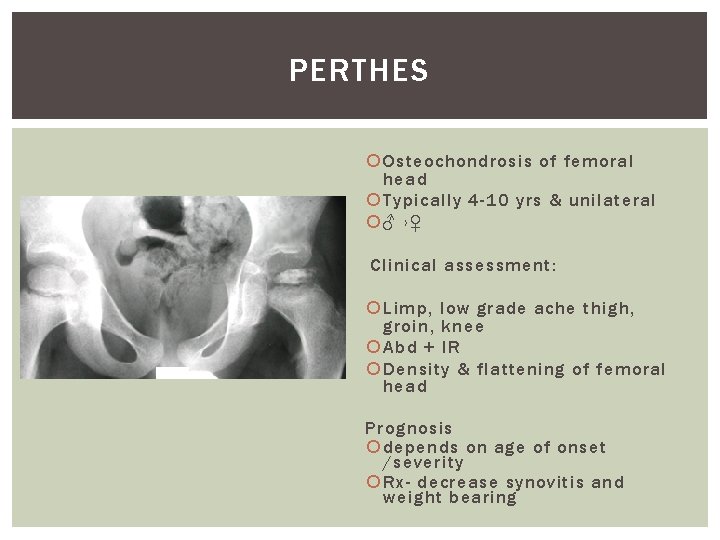

PERTHES Osteochondrosis of femoral head Typically 4 -10 yrs & unilateral ♂ ›♀ Clinical assessment: Limp, low grade ache thigh, groin, knee Abd + IR Density & flattening of femoral head Prognosis depends on age of onset /severity Rx- decrease synovitis and weight bearing